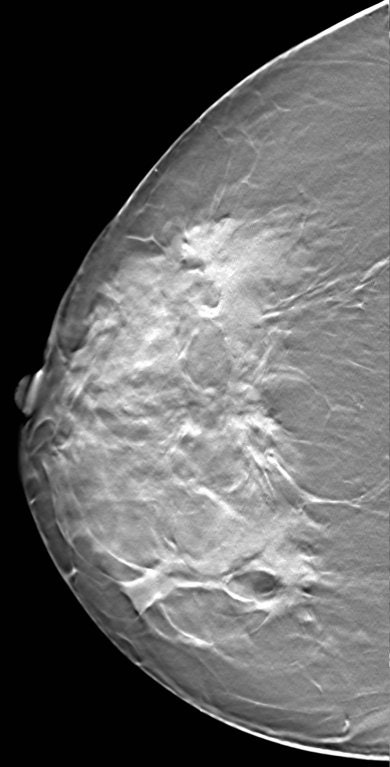

| A breast image collected with XCounter's XC Mammo-3T technology. |

The technique delivers an image that is sharper in detail to CT, using less radiation, Francke said. This is due to the technology's advantage with regard to position resolution and image acquisition. High position resolution helps resolve small details in an image. XCounter's technology also has a particularly short acquisition time, better enabling imaging of dynamic processes (for example, a heartbeat or contrast agent injections), he noted.

"CT cannot resolve very small details; the pixels are fairly large," Francke said. "And second, the dose levels we use are a fraction of CT doses. We can do 3D images with orders of magnitude lower doses than CT uses."

XCounter is developing three products based on the XCT detector. The first, XC Mammo-3T, is for 3D mammography; the second, XC MP-3T, is for 3D general body imaging (as an alternative to CT); and the third is XC Cardio-4T, a 3D cardiac imaging tool for dynamic images.